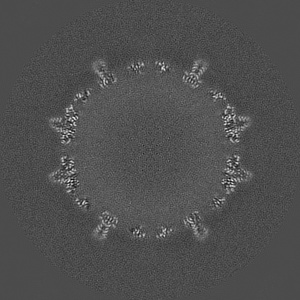

EMD-29858

Single-particle

3.8 Å

Hepatitis B virus capsid bound to importin alpha1

Sample Organism: Hepatitis B virus

Sample: Capsid formed by Cp183 when importin alpha1 is incorporated

Fitted models: 8g8y

Deposition Authors: Yang R , Cingolani G

Structural basis for nuclear import of hepatitis B virus (HBV) nucleocapsid core.

Yang R , Ko YH , Li F , Lokareddy RK, Hou CD , Kim C, Klein S , Antolinez S , Marin JF , Perez-Segura C , Jarrold MF, Zlotnick A , Hadden-Perilla JA , Cingolani G

(2024) Sci Adv , 10 , eadi7606 - eadi7606

PUBMED: 38198557

DOI: doi:10.1126/sciadv.adi7606